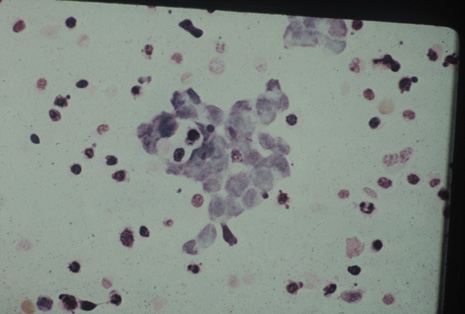

Many forms of uveitis are characterized by specific types of inflammatory cells. Usually, however, one encounters mixtures of cell types in any given specimen, with the relative percentages of lymphocytes and polymorphonuclear leukocytes varying. There may be unusual numbers of eosinophils, or macrophages laden with lens material may be present. Thus, an enumeration of the cells and a careful analysis of their structure can be useful as a diagnostic aid (Figs. 7, 8, 9, 10, 11, 12, 13, 14, 15, 16, 17, 18, 19, and 20). Figure 15 demonstrates eosinophils that were aspirated from the anterior chamber of a patient with Toxocara canis endophthalmitis. Figure 12 demonstrates malignant cell infiltrate from the vitreous, showing the stained presence of monoclonal light chains being elaborated in the cytoplasm. Interleukin-10, detectable in the vitreous of intraocular lymphoma patients, is also directly indicative of both the clinical activity and the number of malignant cells as observed by cytopathology.

Precise identification and culture of bacterial and fungal pathogens from both the aqueous humor and the vitreous fluid can be obtained. Gram's stain and Giemsa's stain smears of centrifuged specimens from the aqueous humor and the vitreous humor frequently demonstrate the bacterial or fungal causative agent. Attempts to isolate bacteria and fungi and to identify them on Gram's stain or Giemsa's stain smears have been most rewarding in the following cases: (a) postoperative endophthalmitis, (b) infection after a penetrating injury of the eye, (c) drug abuse patients with endogenous endophthalmitis (Figs. 21, 22, 23, 24, and 25), (d) patients receiving hyperalimentation, and (4) patients who are immunocompromised as a result of exogenous immunosuppressive agents.